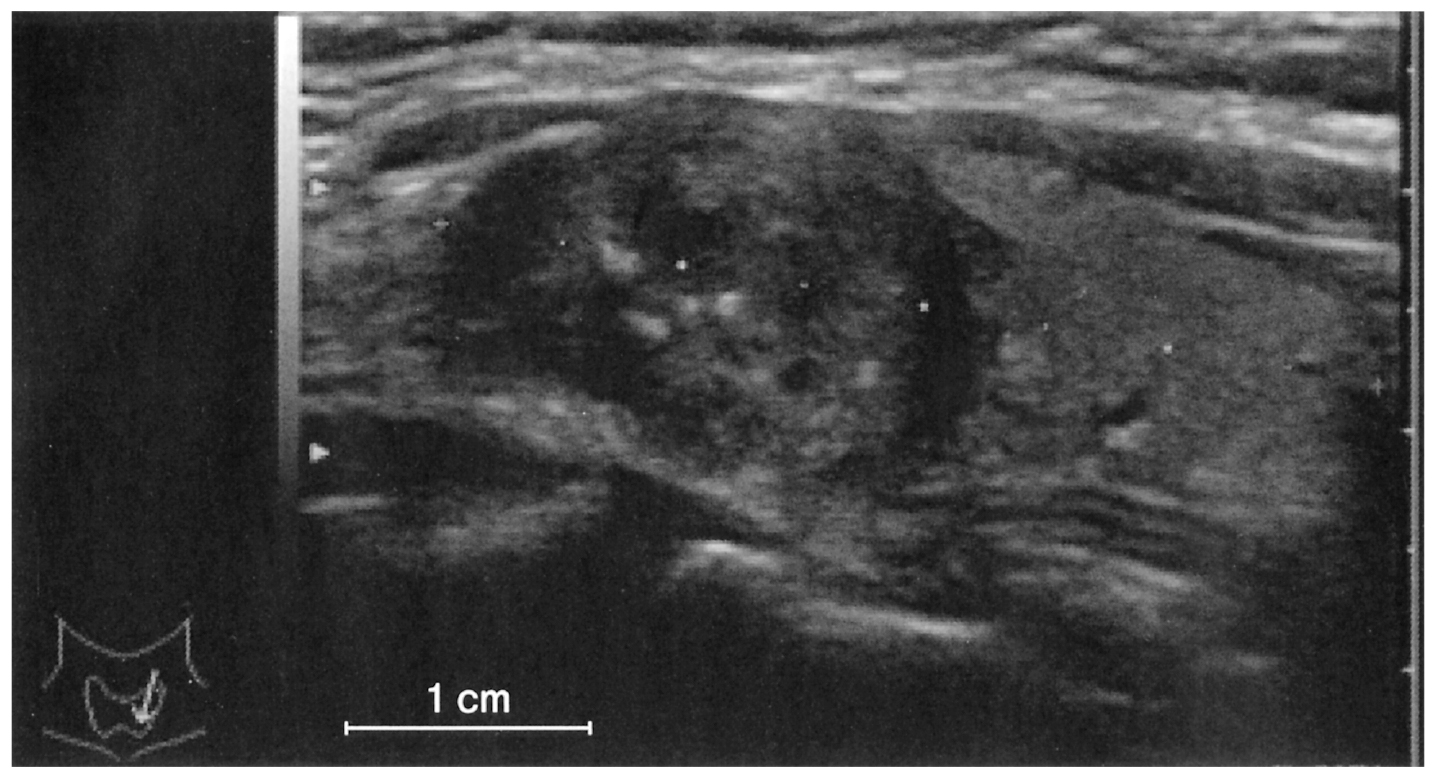

35歳の女性。結節性甲状腺腫を指摘され来院した。身長164cm,体重45kg。脈拍72/分,整。血圧120/76mmHg。甲状腺左葉に小結節を触知し,圧痛を認めない。血液生化学所見:TSH 2.8μU/mL(基準0.2~4.0),FT3 3.4pg/mL(基準2.3~4.3),FT4 1.4ng/dL(基準0.8~2.2)。免疫血清学所見:抗サイログロブリン抗体0.3U/mL未満(基準0.3以下),抗甲状腺ペルオキシダーゼ〈TPO〉抗体0.3U/mL未満(基準0.3以下)。頸部超音波像を下に示す。